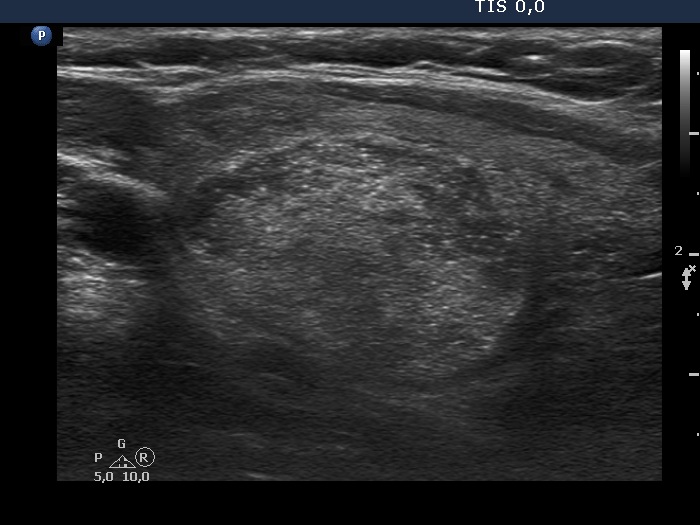

Oxyphilic adenoma (histological diagnosis) - case 1735 |

Papillary carcinoma (histological diagnosis) |

Both lesions have multiple cystic areas. The malignant case clearly belongs to spongiform cyst category because the cystic area exceeds 50% of the nodule. The risk of malignancy is very low in such lesions if there are no signs suggesting an increased risk. The solid part was hypoechogenic in these cases therefore aspiration cytology was mandatory. Note that both cases presented signs of posterior acoustic enhancement, i.e. hyperechogenic figures in the back wall of the microcystic areas. There was only one but an important difference between the cases. The benign nodule was located within the thyroid, while the malignant was found in a lateral aberrant thyroid tissue.